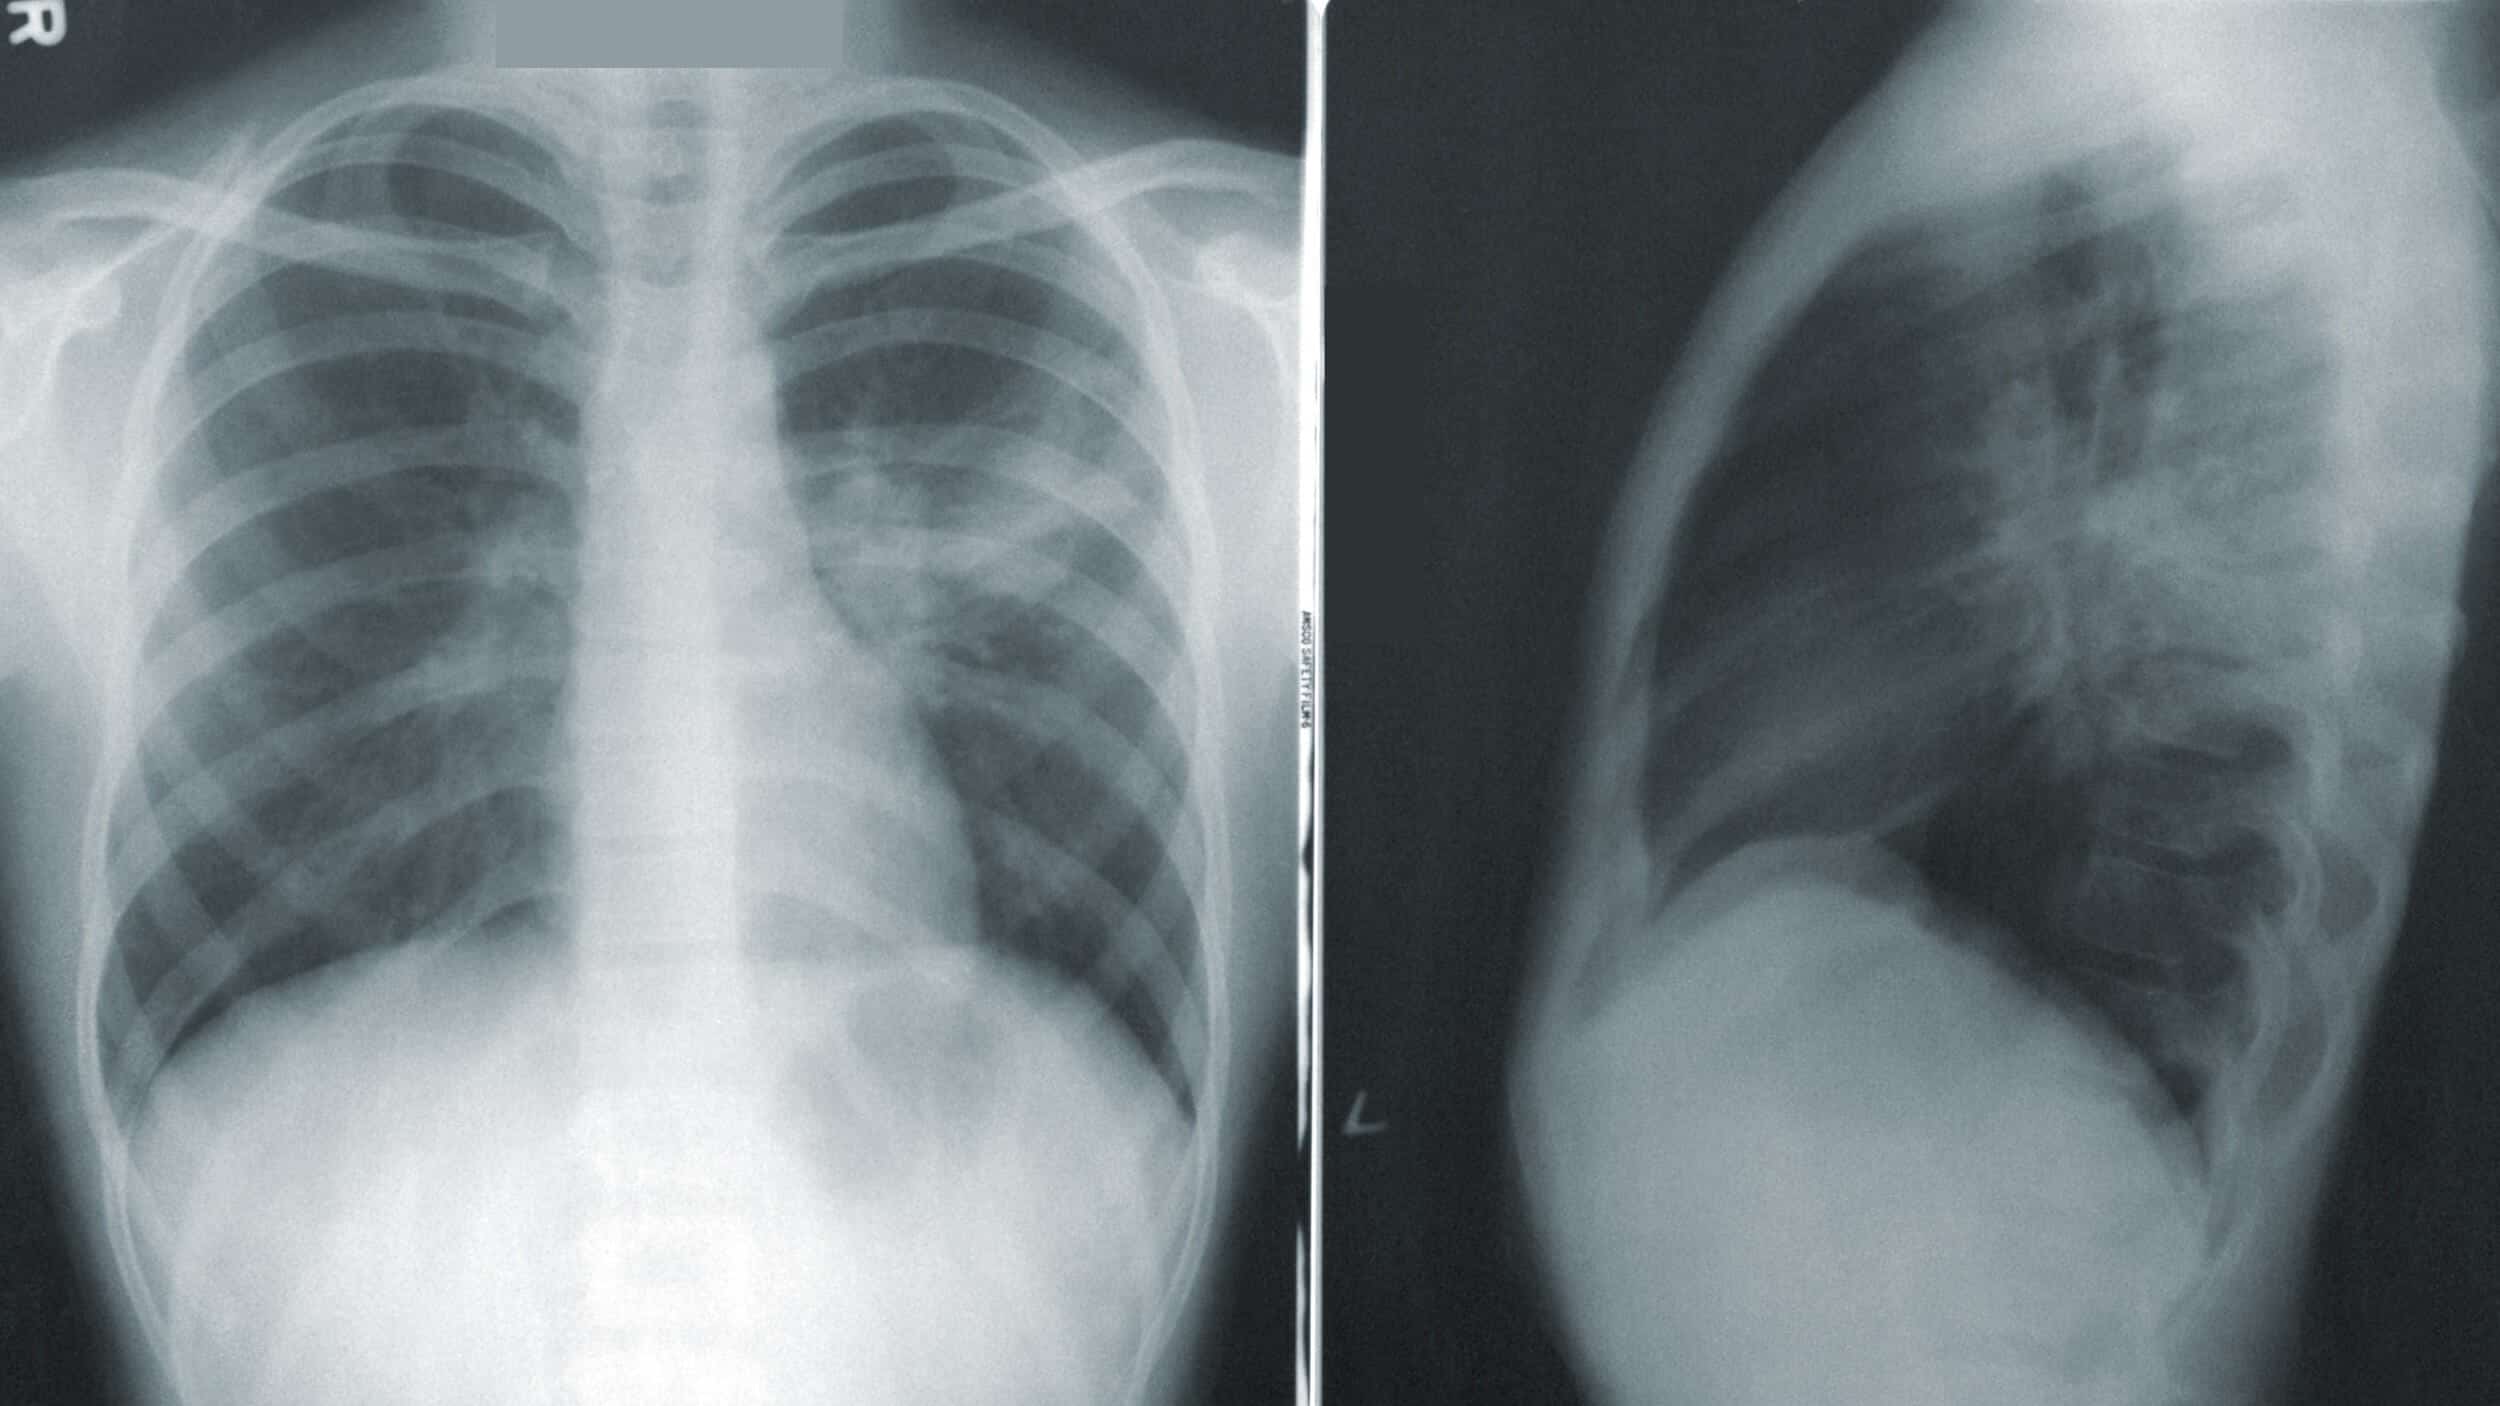

تصوير الصدر بالأشعة السينية Mayo Clinic مايو كلينك

الأشعة السينية هي اختبار تصوير يساعد على سرعة التشخيص Mayo Clinic مايو كلينك

الأشعة السينية هي اختبار تصوير يساعد على سرعة التشخيص Mayo Clinic مايو كلينك

اطمن على نفسك الأشعة على الصدر تساعد فى تشخيص أمراض القلب اليوم السابع

Pneumonia Radiology Reference Article Radiopaedia Org